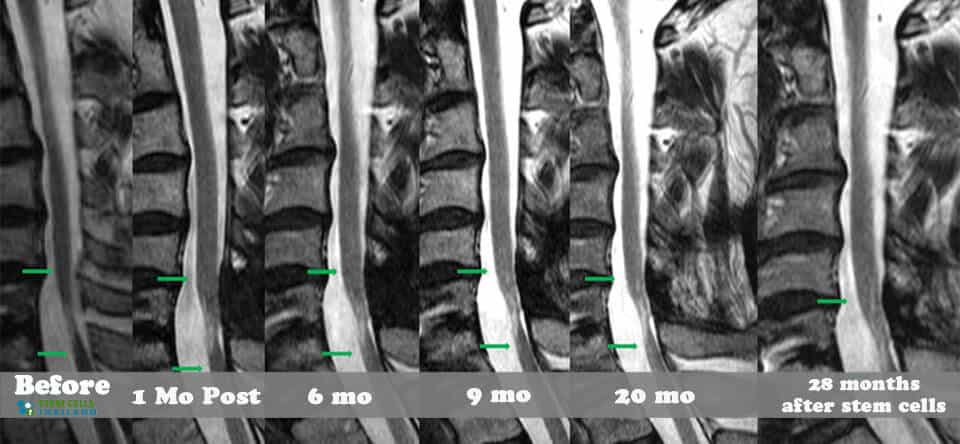

The objectives of our spinal injury treatment center is to help repair damage in a natural and safe manner. Our treatments take place on the cellular level and only affect the areas near to the point of impact. Positive results can be pretty dramatic if the injury is less than 2 years ago. For those with older injuries, traumatic brain injuries, severely degenerative spinal discs, osteonecrosis, peripheral neuropathy or spinal muscular atrophy the chances of full recovery become significantly more difficult with passing time. Newer injuries to tissue, cartilage or ligaments respond much better to stem cell treatments. The recovery after treatment will require a lot of dedication and rehabilitation sessions. Physical improvements are noticeable around 2-3 months after the initial treatment and the results are permanent.[2]